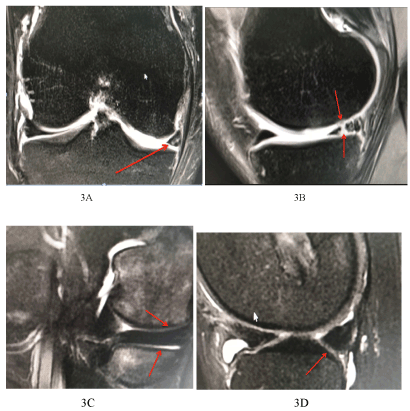

Figure 3. 40-year-old patients with ACL reconstruction, right knee, coronal and sagittal sections showing in posterior horn medial meniscus complex tear with radial component with extension to both articular surfaces. Post injection of chondrocytes, Figure 3 C and D demonstrate total healing of the meniscus with no signals showing any rent in the meniscus